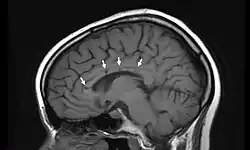

Enzephalopathie und MRT-Veränderungen

Kognitive Störungen sind Veränderungen des Denkens, die bis zu einer Psychose reichen können. Häufig tritt begleitend starker Kopfschmerz auf, der den weiteren Symptomen vorausgehen kann. In der obligaten Magnetresonanztomografie bestehen nahezu immer typische Defekte im Balken.[5] Dort findet man Veränderungen typischerweise im Bereich der zentralen Bahnen mit relativer Aussparung der Balkenperipherie. Weitere Gehirnareale können befallen sein.